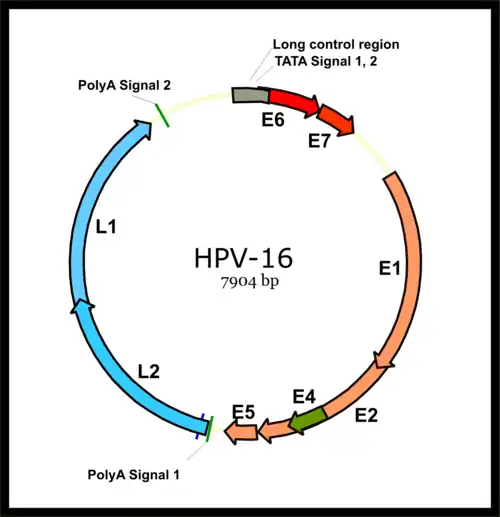

HPV-associated cancers are caused by high-risk strains of HPV, mainly HPV-16 and HPV-18.[35] HPV is a small non-enveloped DNA virus of the papillomavirus family. Its genome encodes the early (E) oncoproteins E5, E6 and E7 and the late (L) capsid proteins L1 and L2. The virus gains access to the mucosa through microlesions, where it infects the basal layer of cells, which are still able to proliferate. While the virus does not replicate in these cells, expression of its early genes stimulates proliferation and lateral expansion of the basal cells. As this moves the virus particles into the overlying suprabasal layers, late viral gene expression occurs, enabling replication of the circular viral genome (see figure) and structural proteins. As these are pushed into the most superficial mucosal layers, complete viral particles are assembled and released.[36]

An increased risk of HPV+OPC is observed more than 15 years after HPV exposure,[8] pointing to a slow development of the disease, similar to that seen in cervical cancer. Relative to HPV-OPC, the oncogenic molecular progression of HPV+OPC is poorly understood.[28] The two main viral oncoproteins of the high risk HPV types are E6 and E7. These are consistently expressed in malignant cell lines, and if their expression is inhibited the malignant phenotype of the cancer cells is blocked. Either of these oncoproteins can immortalise cell lines,[37] but are more efficient when both are expressed since their separate molecular roles are synergistic.[35][36] The E6 and E7 oncogenes become integrated into host-cell DNA, and the oncoproteins they express interfere with a variety of predominantly antiproliferative cellular regulatory mechanisms. They bind to and inactivate the best known of these mechanisms, the tumor suppressor proteins p53 and retinoblastoma protein pRB (pRb) leading to genomic instability and then cell cycle deregulation (see Chung et al., 2016 Fig. 35.2).[28] Further, yet to be elicited, mechanisms are required for the final steps of malignant transformation of HPV infected cells.[28]

HPV- and HPV+OPC are distinguishable at the molecular level. The naturally occurring (wild type) p53 is widely involved in cellular processes, including autophagy, response to DNA damage, cell cycle regulation, and senescence, apoptosis and the generation of adenosine triphosphate (ATP) through oxidative phosphorylation.[38] The gene encoding p53 is inactivated by E6 at the protein level and is found as the wild type in HPV+OPC but mutated in HPV-OPC. In HPV+OPC p53 protein undergoes accelerated degradation by E6, drastically reducing its levels, while in HPV-OPC it undergoes genetic mutation, which may result in synthesis of an abnormal p53 protein, that may not only be inactive as a tumour suppressor but can also bind and inactivate any non-mutated wild type p53, with an increase in oncogenic activity.[39] Although p53 mutations occur in HPV+OPC, they are far less common than in HPV-OPC (26% vs 48%), and do not appear to affect clinical outcome.[40]

The pRb protein is inactivated by E7 in HPV+OPC, but in HPV-OPC, it is the p16 tumour suppressor part of the pRb tumour suppressor network that is inactivated. Also the pRb pathway is inactivated by E7 instead of Cyclin D1 amplification.[8][41] CDKN2A is a tumour suppressor gene that encodes a tumor suppressor protein, p16 (cyclin-dependent kinase inhibitor 2A) and inhibits the kinase activity of the cyclin-dependent kinases CDK4 and CDK6, which in turn induce cell cycle arrest.[38] p16 expression is cell cycle-dependent and is expressed focally in only about 5–10% of normal squamous epithelium. Like most HPV+ cancers, HPV+OPC express p16 but the latter does not function as a tumour-suppressor, because the mechanism by which this is achieved, pRb, has been inactivated by E7. p16 is upregulated (over-expressed) due to E7-related loss of pRB with reduced negative feedback,[39][42] whereas it is downregulated in up to 90% of HPV-OPC.[43] This diffuse over-expression in the tumour cells provides a diagnostic marker for HPV involvement.[44][45] Although HPV E6 and E7 reduce tumour suppressor activity, they do so less than genetic and epigenetic processes do in HPV-OPC.[46][47][11]